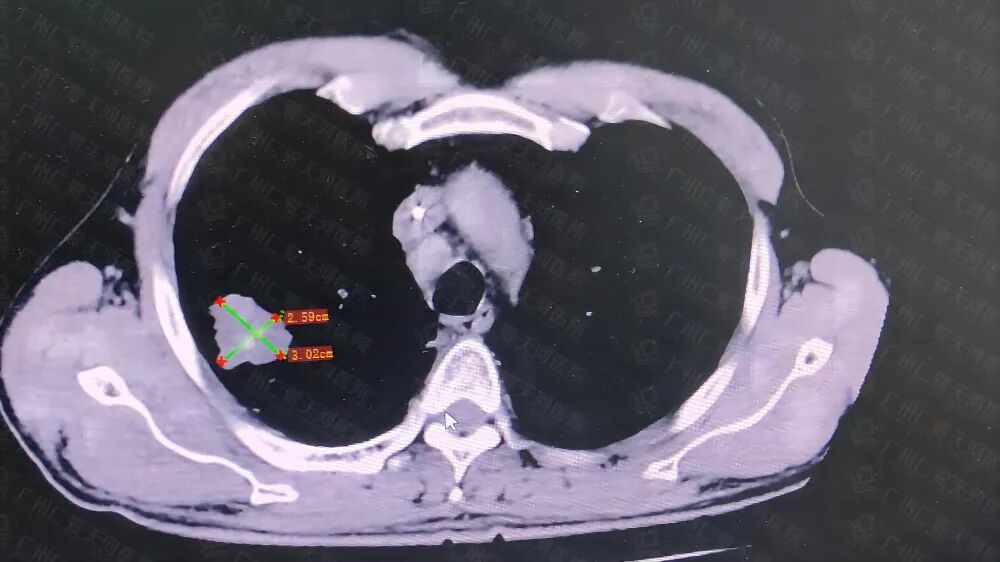

治疗后复查CT显示肿瘤已明显缩小▲

在宋主任带领的肿瘤综合诊治专家团队和介入科的共同协作下,对该患者进行了肿瘤精准微创介入联合疗法。手术非常顺利。经治疗后,患者咳嗽、咳痰、气促症状明显改善,术后一周复查胸部CT示肿瘤病灶较入院时明显缩小,评估治疗显效,病情好转,已于近日出院。

收治入院后行右上肺肿物穿刺活检,确诊为“右上肺恶性肿瘤(小细胞癌)并双肺、纵膈、颅内多发转移瘤”。